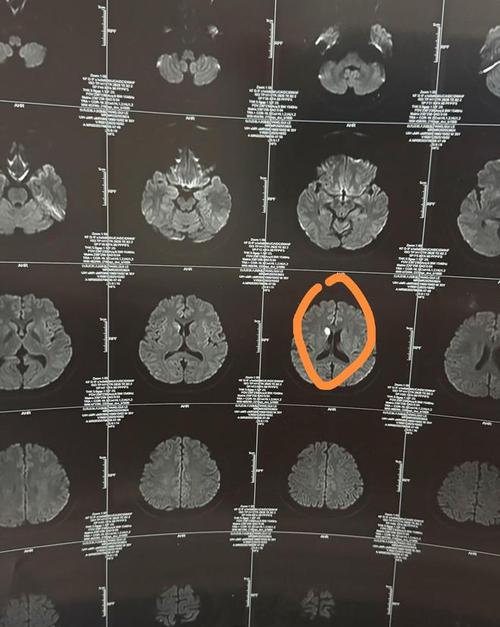

“右边脑梗一年后左边脑梗”意味着患者在大脑右侧发生了一次脑梗塞,经过一年时间后,大脑的左侧又发生了新的梗塞,这被称为复发性脑卒中。

这表明患者脑梗塞的根本原因可能没有得到有效控制,或者存在新的诱因,复发性脑梗的病情往往比首次更严重,致残率、致死率都更高,因此必须引起高度重视。

- 全面检查:入院后,医生会安排头颅CT/MRI、颈部血管超声/CTA/MRA、心脏超声、血液化验(凝血功能、血脂、血糖等)等一系列检查,以明确这次梗塞的原因、位置和范围,并评估全身状况。